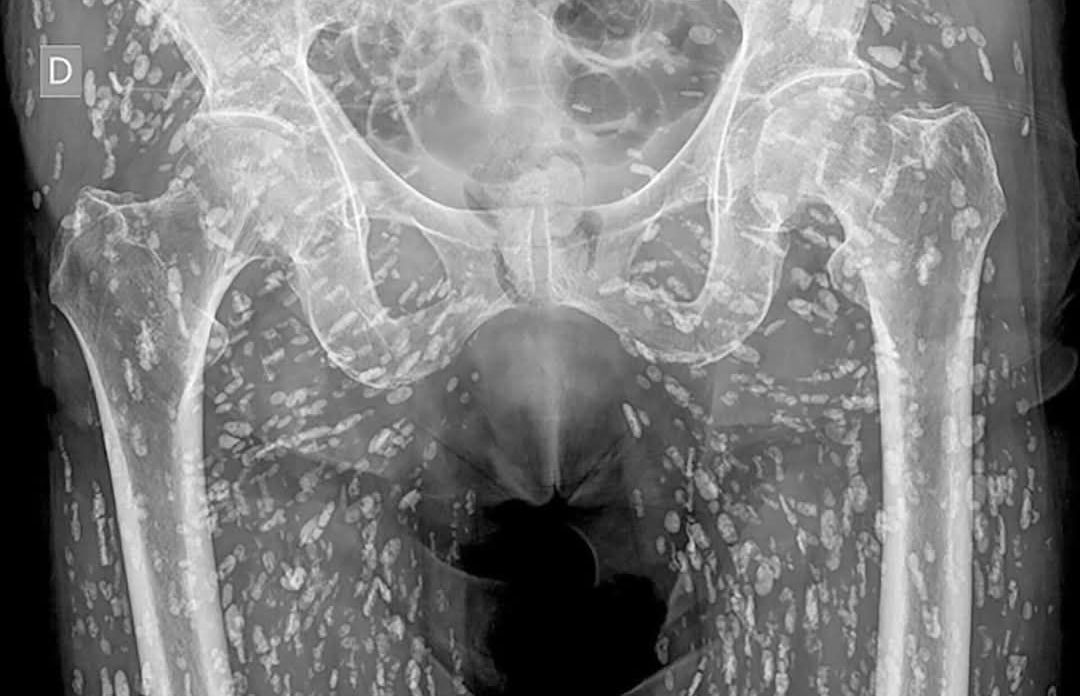

據泰媒《Khaosod》報導,這名婦人8年前接受X光檢查,影像結果卻顯示密密麻麻的白點,放射科醫生研判這些白點都是寄生蟲,布滿她的臀部到腿部,並強調這通常是長期食用生食和生肉所致,這番噁心的影像讓原PO感到十分毛骨悚然,甚至不斷用酒精清潔雙手。